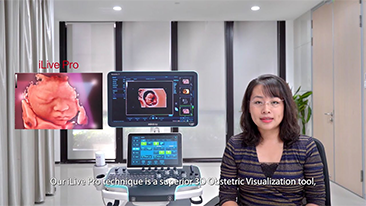

AlimentÊe par la plateforme avancÊe ZST+, la gamme complète de solutions intelligentes Nuewa est con?ue spÊcialement pour amÊliorer la santÊ des femmes avant, pendant et après la grossesse, de manière à poser des diagnostics complets et efficaces pour rÊpondre à des dÊfis cliniques de plus en plus exigeants.